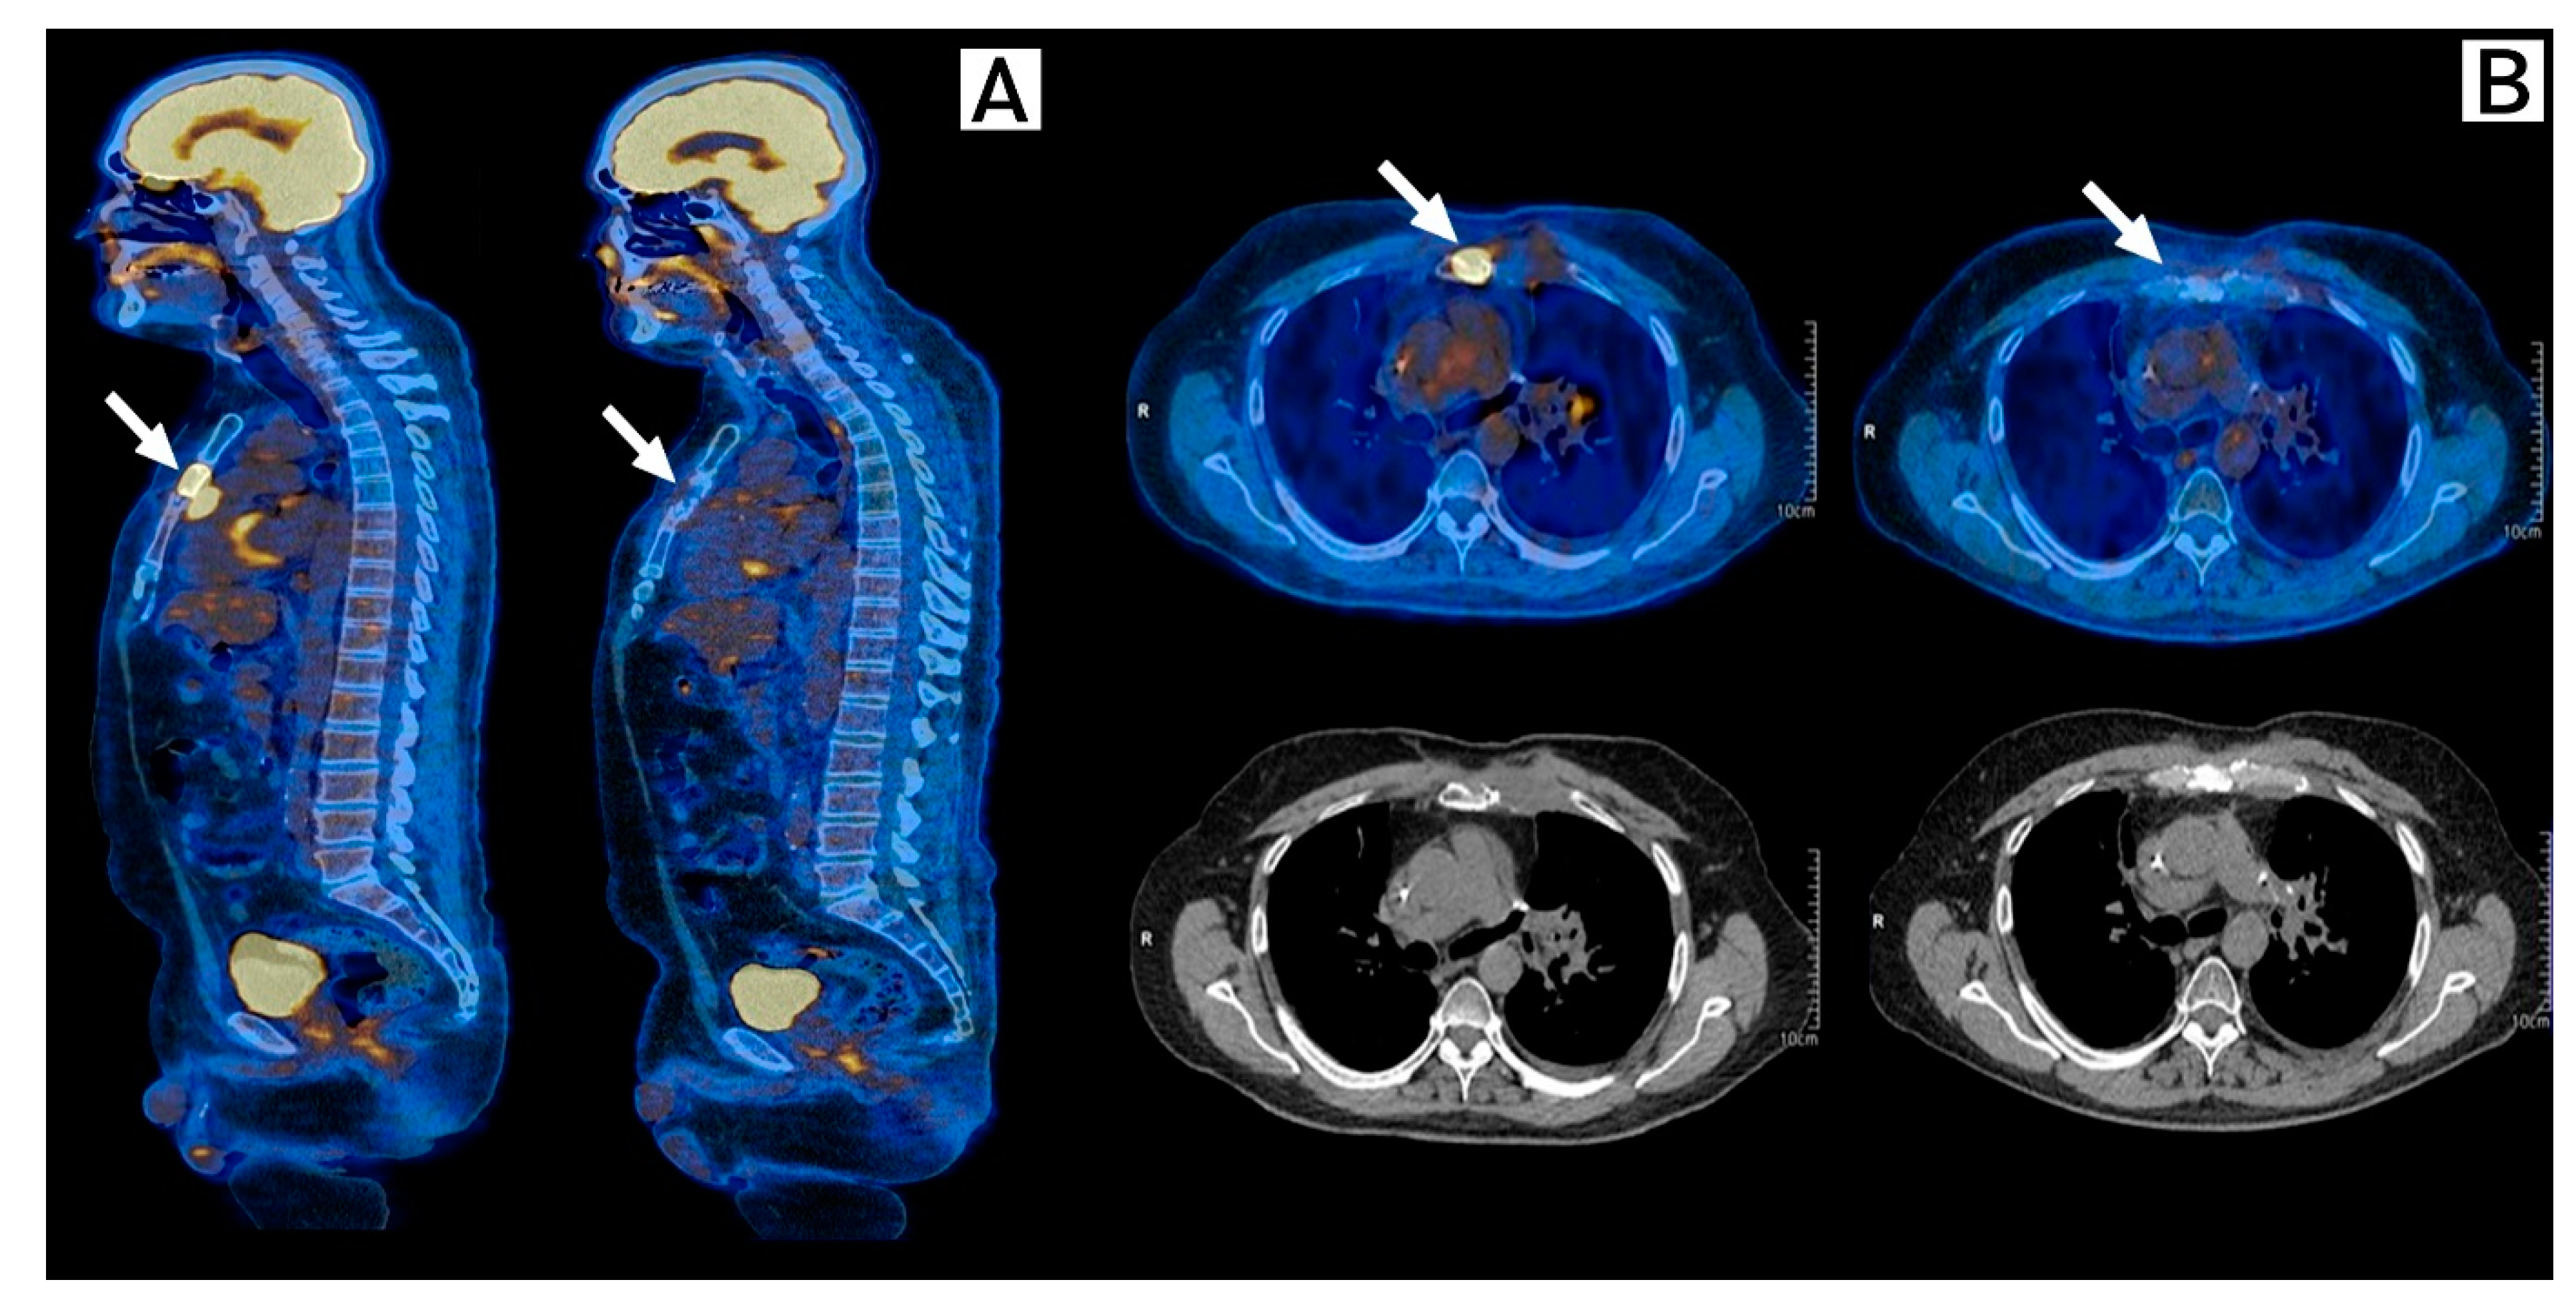

2. Case Description